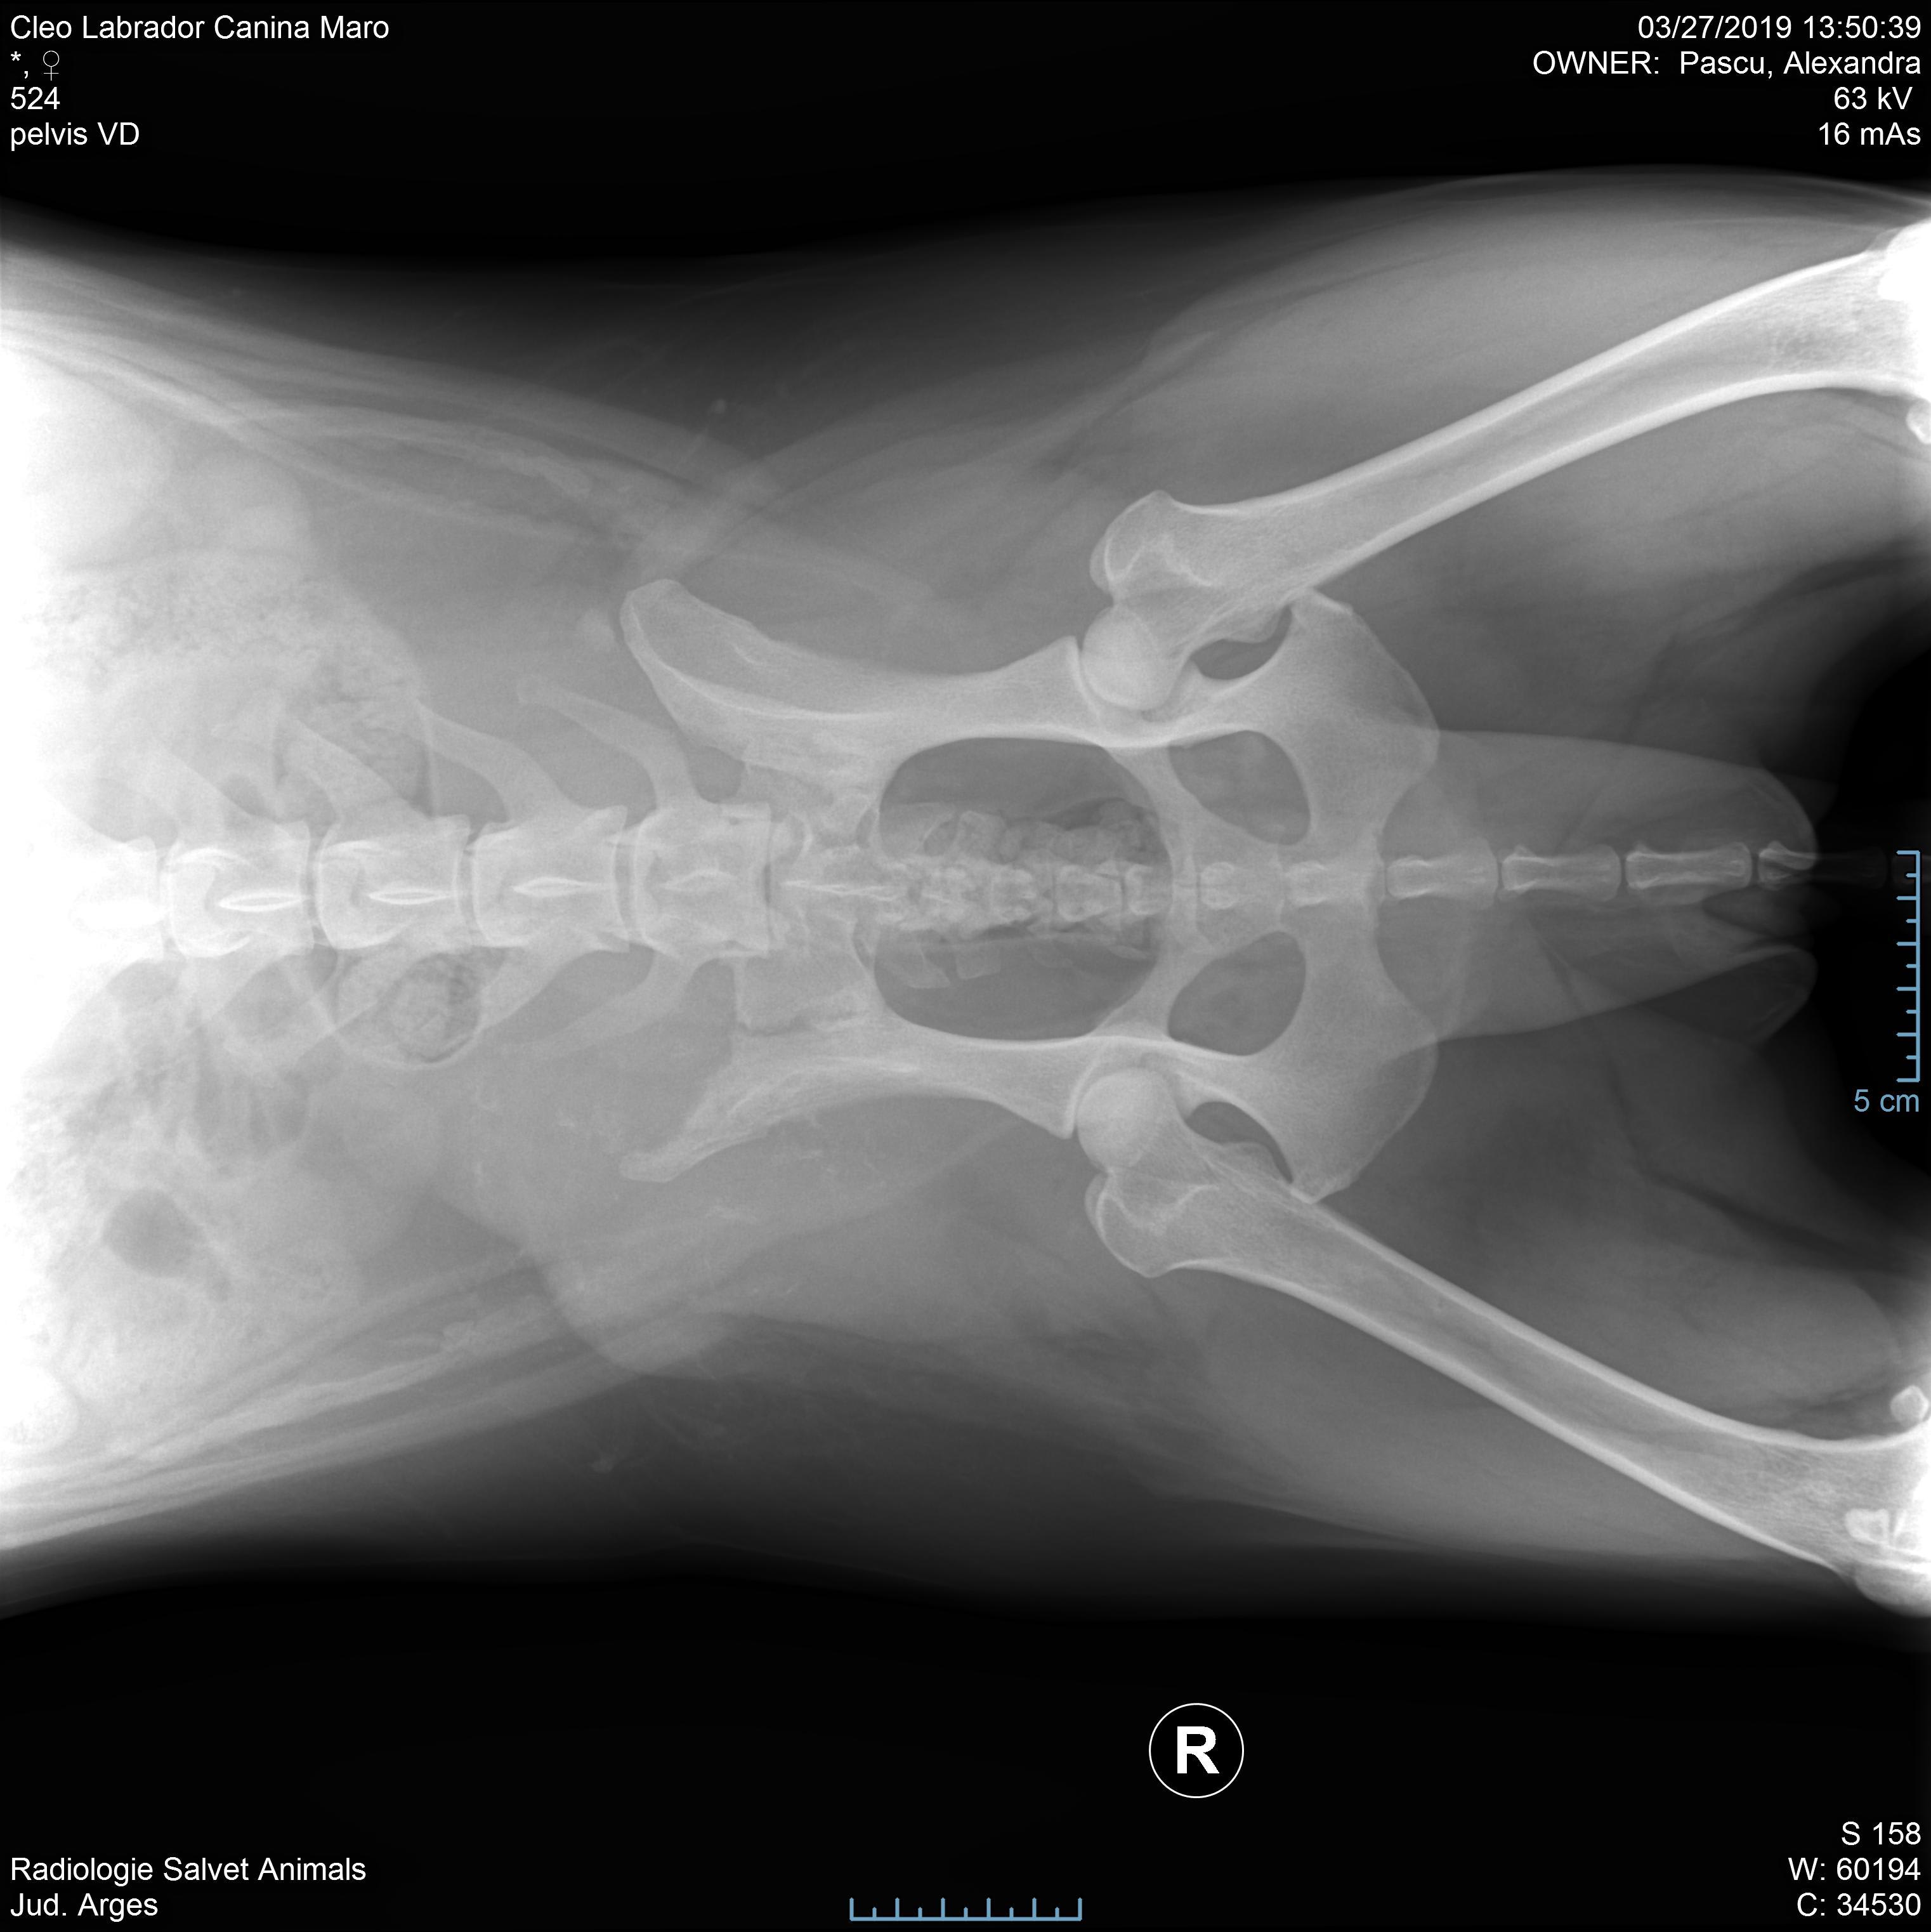

Pet's info: Dog | Labrador Retriever | Female | unspayed | 3 years and 3 months old | 36 lbs

Hi! I'm desperate to hear a second opinion about my dog case. I attached her x-Ray. The doctors said it could be something oncological as she has that injury without being Hurt. I'm about to go with her for more tests. Please help me with an advice.

Hello. That is definitely a swelling that should be further investigated. Given her age, hopefully this is something benign, but you should continue with testing to see what is going on. Hope she is well soon & thanks for using Petco Pet Education Center, formerly Petcoach.